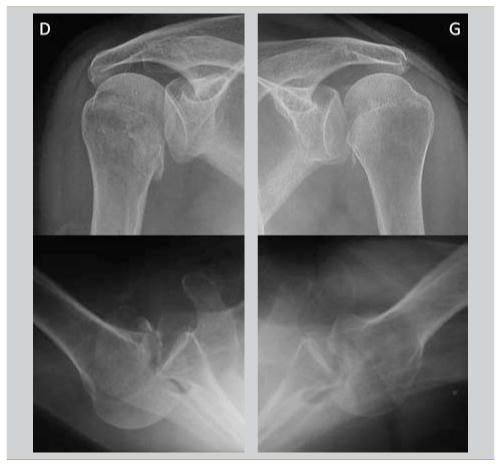

2 réponses Réponse 1 / 2 DCI Messages postés Date d'inscription mercredi 30 avril 08 Statut Modérateur Dernière intervention 1 avril 21 28 472 13 août 10 à 1809 Bonjour, Seul les examens radiographiques peuvent donner la réponse (suites d'une malformation Bankart, Luxation Epaule J'ai subit une opération Bankart il y a 9 mois pour des pb de luxation de l'epaule et j'ai du mal a récupérer (tendinite, inflamation de l'epaule, névralgies) dès que je sollicite trop l'articulation Qq as il un avis et une expérience similaire pour savoir quel sont les temps de récupérationLuxation souscoracoïdienne c'est la plus fréquente, où la tête se retrouve audessous de la coracoïde Luxation intracoracoïdienne la plus rare, dans ce cas, le déplacement est majeur Luxation postérieure (4%) plus rare Mécanisme choc direct sur la face antérieur de l'épaule, rotation interne forcée du bas

On parle de luxation de l'épaule lorsque la racine du bras (tête de l'humérus) se déboite hors de sa cavité située dans l'omoplate Ils existent 2 types de luxations la luxation antérieure et la luxation postérieure La luxation antérieure ou antérointerne (LAI) est de loin la plus fréquente (95%), la tête de l'humérus se La luxation de la hanche, ou dysplasie développementale de la hanche (DDH) touche environ 1 bébé sur 1000 En outre, un nouveauné sur trois présente une petite instabilité auUne épaule démise est différente d'une luxation acromioclaviculaire Cette dernière est une entorse du ligament dans l'articulation qui relie la clavicule à la ceinture scapulaire L'articulation glénohumérale n'est pas démise

On Vous propose 3 exercices pour luxation de l'épaule Bien sûr ses exercices on peut utiliser aussi avec la problème de la coiffe rotateurs Prezentujemy WaLa luxation antérieure d'épaule est de loin la plus fréquente Il existe plusieurs catégories de luxations d'épaule 1 les luxations posttraumatiques lors d'une chute sur le bras ou lors d'un mouvement en armé contré, la tête humérale se luxe en avant de la glène Pendant ce traumatisme, des lésions des tissus entourantLes signes de luxation de l'épaule sont L'impression de « déboîtement articulaire » qui est généralement bien décrite par la personne blessée La douleur une luxation d'épaule est très douloureuseLa personne blessée se présente alors spontanément dans la position qui la soulage le plus, c'estàdire le bras plaqué contre le thorax avec le coude plié et l'avantbras soutenu

Définition qu'estce qu'une luxation de l'épaule ?La luxation ou instabilité de l'épaule (luxation glénohumérale) est une pathologie fréquemment rencontrée (2 % de la population) Elle nécessite le plus souvent une opération afin d'éviter une instabilité chronique avec des récidives Les luxations antérieures représentent près de 95 % des cas et concernent majoritairementLuxation de la hanche chez le bébé définition Le terme luxation de la hanche décrit une condition dans laquelle, dans l'articulation de la hanche du bébé, la tête de la cuisse ne s'accroche plus dans la cavité de la hanche et en glisse, de sorte que les partenaires articulaires impliqués ne sont plus physiologiquement connectés